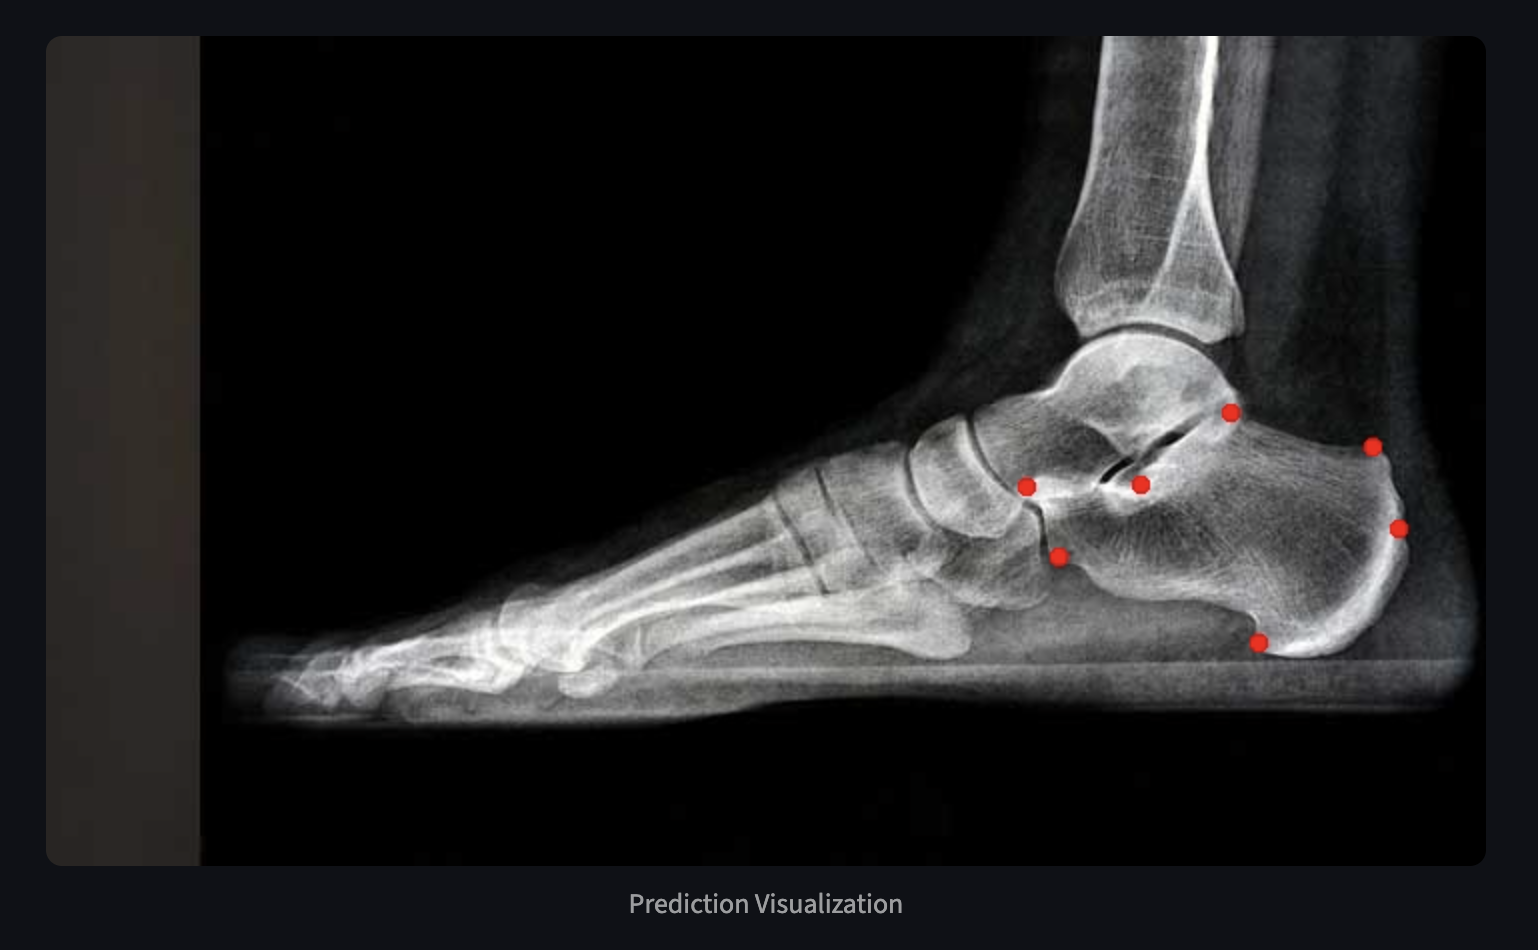

Abstract on autolabeling of foot and ankle anatomy accepted for poster presentation.

Implemented CNNs for anatomical landmark detection on 3000+ radiographs. Achieved 94% SDR with Grad-CAM interpretability, reducing surgeon review time by 30%.